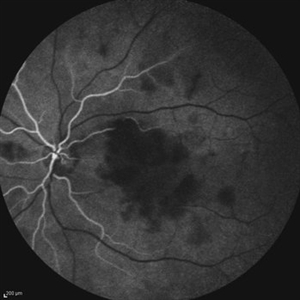

Idiopathic Occlusive Retinal Vasculitis (Late Stage) Idiopathic Occlusive Retinal Vasculitis (Late Stage)May 31 2014 by Hamid Ahmadieh, MD FAF image of the left eye of a 28-year-old woman with idiopathic occlusive retinal vasculitis 6 months after the onset. Patches of hard exudate are present superior to the fovea. Photographer: Elham Salehi, Negah Eye Center, Tehran Imaging device: Heidelberg Spectralis Condition/keywords: fundus autofluorescence (FAF)

Idiopathic Occlusive Retinal Vasculitis (Late Stage) Idiopathic Occlusive Retinal Vasculitis (Late Stage)May 31 2014 by Hamid Ahmadieh, MD Wide-field FA image of the left eye of a 28-year-old woman with idiopathic occlusive retinal vasculitis 6 months after the onset. Photographer: Elham Salehi, Negah Eye Center, Tehran Imaging device: Heidelberg Spectralis Condition/keywords: capillary closure, macular infarction

Idiopathic Occlusive Retinal Vasculitis (Late Stage) Idiopathic Occlusive Retinal Vasculitis (Late Stage)May 31 2014 by Hamid Ahmadieh, MD Late phase FA image of the left eye of a 28-year-old woman with idiopathic occlusive retinal vasculitis 6 months after the onset. Photographer: Elham Salehi, Negah Eye Center, Tehran Imaging device: Heidelberg Spectralis Condition/keywords: capillary closure

Idiopathic Occlusive Retinal Vasculitis (Late Stage) Idiopathic Occlusive Retinal Vasculitis (Late Stage)May 31 2014 by Hamid Ahmadieh, MD Mid- venous phase FA image of the left eye of a 28-year-old woman with idiopathic occlusive retinal vasculitis leading to extensive capillary closure macular infarction and collaterals 6 month after the onset. Photographer: Elham Salehi, Negah Eye Center, Tehran Imaging device: Heidelberg Spectralis Condition/keywords: capillary closure